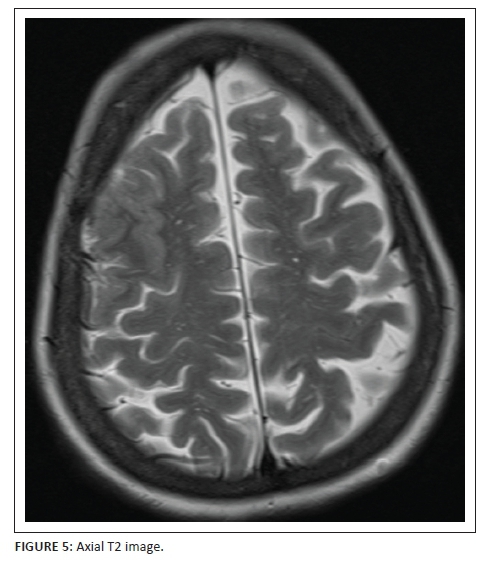

MRI study of the brain was arranged to further elucidate the cause of this unusual presentation. T2-weighted (Figure 5) and T1-weighted (Figure 6) MRI sequences confirmed the right frontal gyral swelling with effaced right middle and superior frontal sulci. Subtle gyral swelling was also observed in the parasagittal left frontal precentral region. Figure 7, a coronal FLAIR image showed, in addition to the frontal gyral swelling, an extra-axial fluid collection over the right frontal lobe convexity and in the sulci due to a sliver of subdural and subarachnoid blood respectively. A right sublenticular cyst was also incidentally noted.